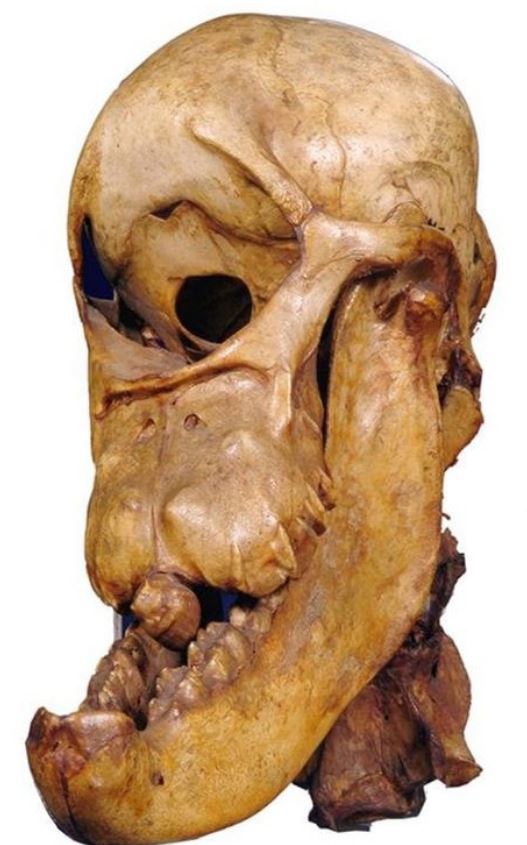

Xương sọ của một con ngựa một mắt.